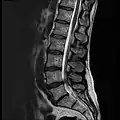

MRI